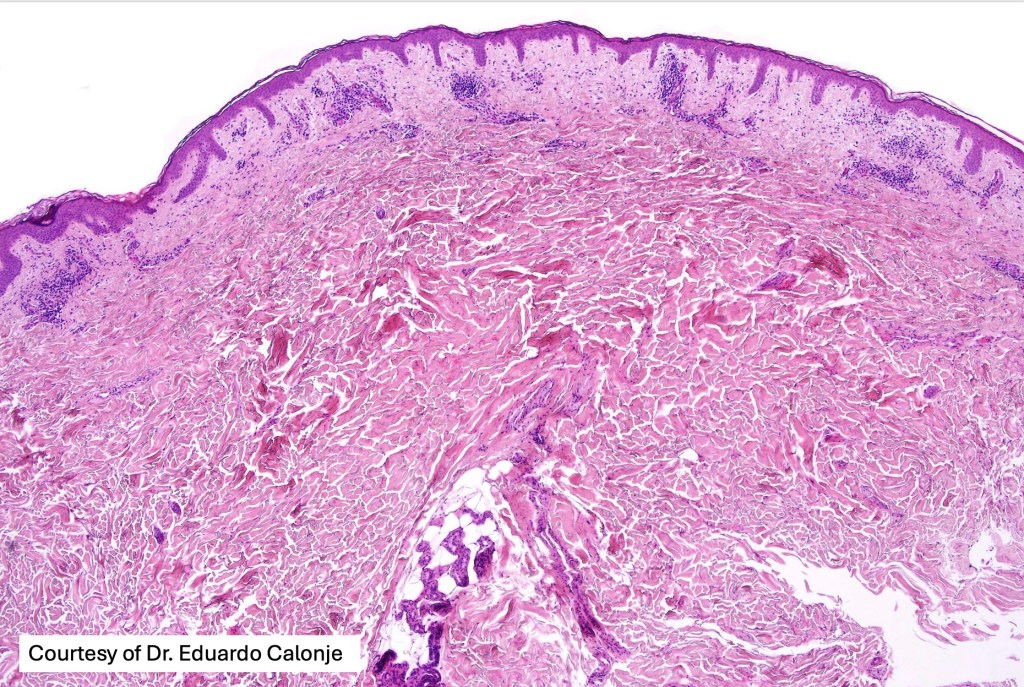

Histological features

•Variable histological features ranging from a non-specific superficial perivascular or band-like dermal infiltrate with minimal or no epidermotropism through to mycosis fungoides-like histology; can mimic atopic dermatitis